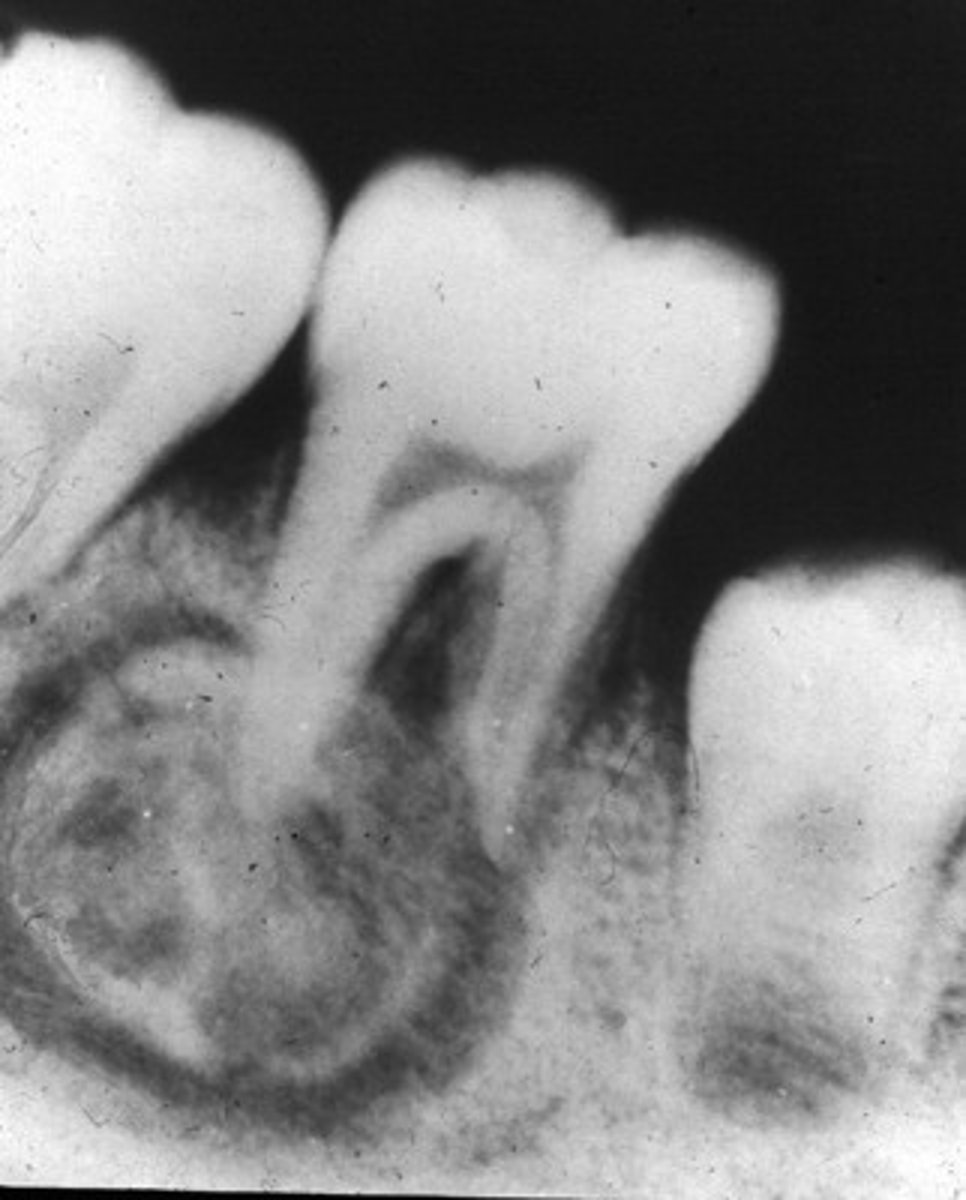

cementoblastoma

-common locations

-clinical features

-radiographic

-population

common locations: mand 1st molar

clinical features: it presents w pain

radiographic: it is a dense radiopaque mass that binds w the apex; it is a sclerotic mass w a thin radiolucent rim; vital teeth are involved

population: children + YA <30s